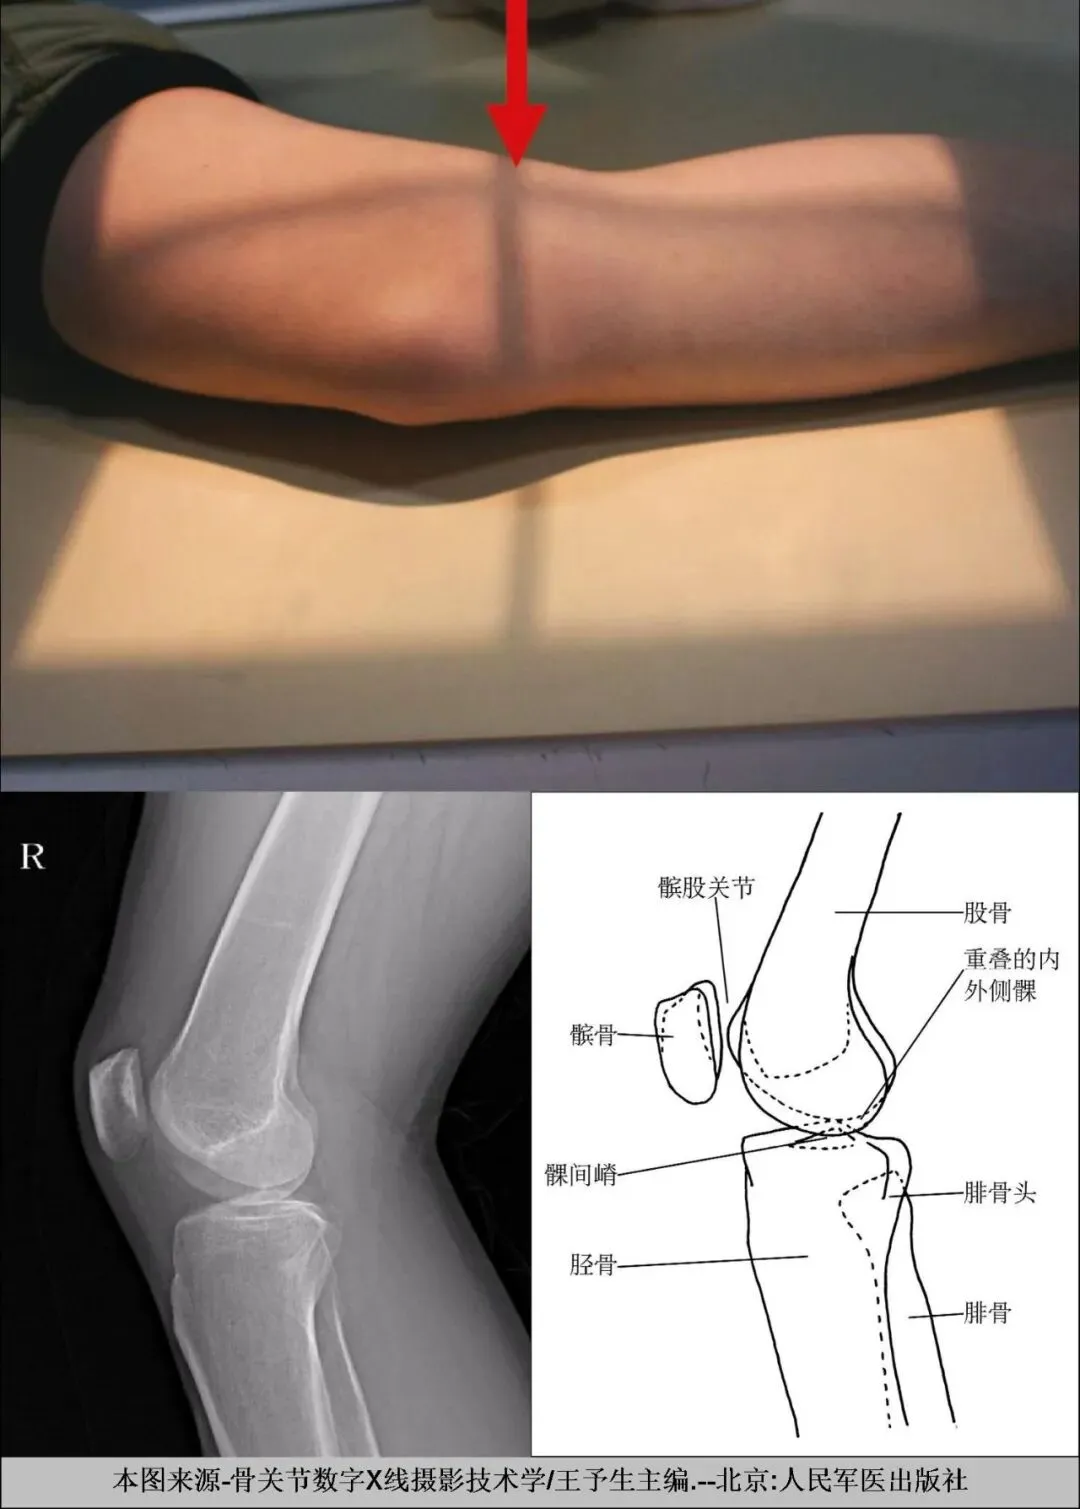

B、膝关节侧位X线摄影要点:

一.体位设计

1. 患者侧卧于摄影台上,对侧膝部弯曲置于被检侧肢体前上方。被检侧膝部外侧靠近台面,膝关节屈曲120°-135°角。

2.髌骨下缘置于探测器中心,髌骨面与探测器垂直。

二.中心线

对准髌骨下缘与腘窝皮肤皱褶线之中点,垂直探测器射入中心。

四.图像质控

1. 膝关节间隙位于影像正中,股骨内外髁重叠良好。

2.髌骨呈侧位显示,与股骨间隙分离明确,关节面边界锐利,无双边。

3.股骨与胫骨平台重叠极小。

正位:观察膝关节间隙,股骨内、外侧髁,胫骨内、外髁,髌骨的骨质、外形变化,膝部软组织、骨骺和籽骨等情况。

侧位:观察膝关节侧位影像,髌骨、股骨下端、胫腓骨上端骨质情况,软组织影像等。